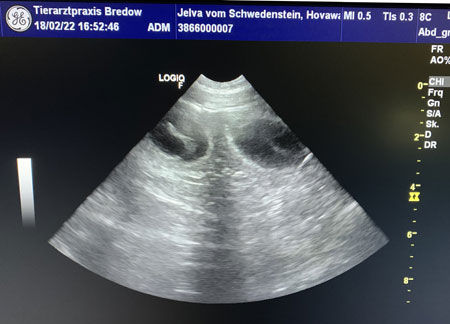

18.02.2022

(27.Tag) - Ultraschalluntersuchung

Die Ultraschalluntersuchung am 27.

Tag ihrer Trächtigkeit bestätigte das was wir schon annahmen. Jelva's

Verhalten in den letzten Tagen deutete es schon an, nun haben wir

Gewissheit, sie ist tragend und wir freuen uns auf unseren M-Wurf. Es waren

mehrere Fruchtblasen zu sehen. Die Aufnahme unten zeigt zwei Fruchtblasen

mit ihren Föten. Wir sind gespannt auf das was kommt...